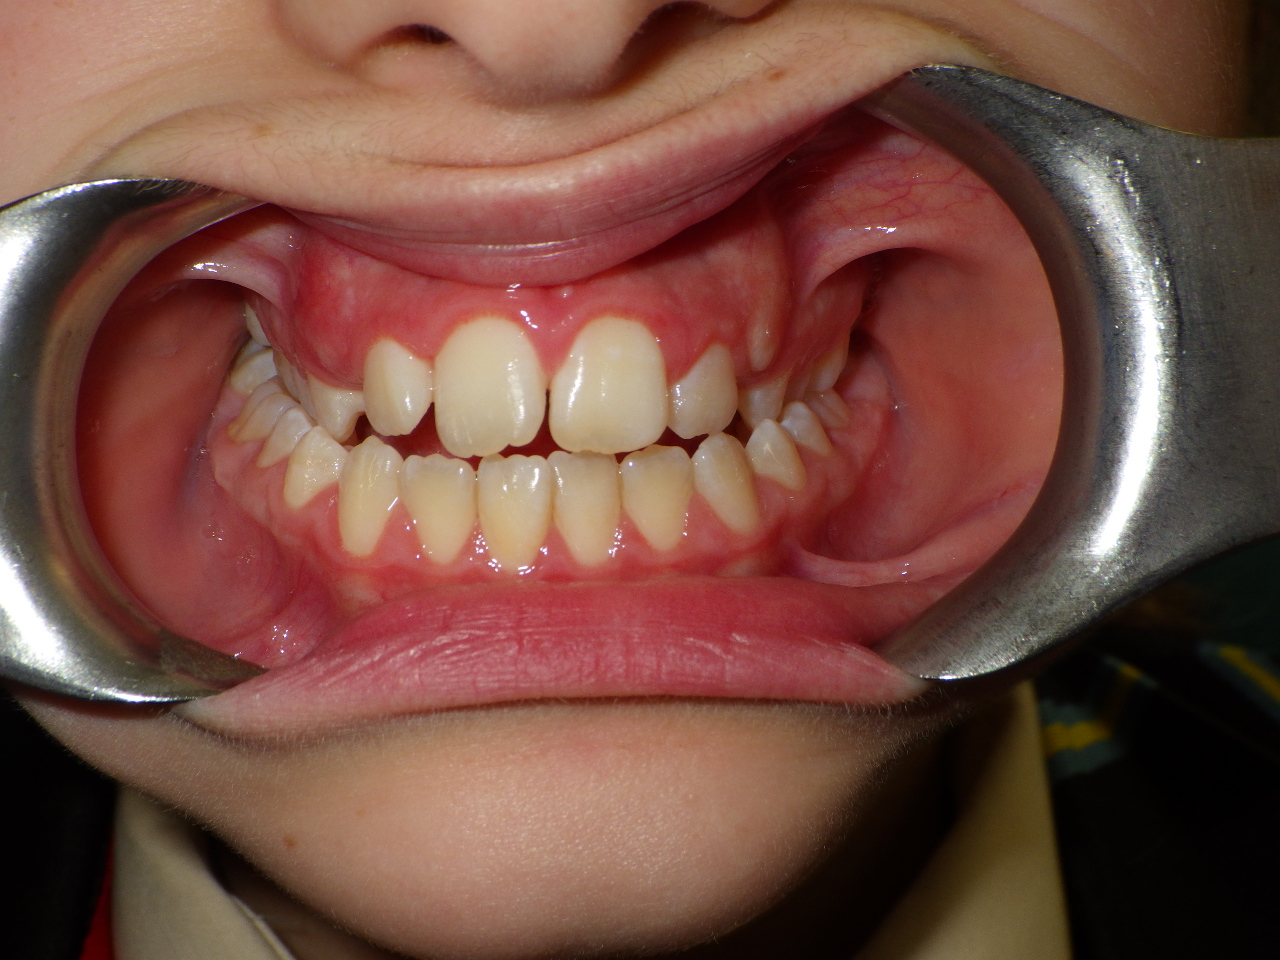

Patient Resultsنتائج المرضى

Real Results. Real Patients.نتائج حقيقية. مرضى حقيقيون.

Airway-centred orthodontics aligns teeth while expanding jaw structure — creating a broader smile, better breathing, and lasting facial harmony without surgery.تقويم الأسنان المتمحور حول الهوائي يُقوّم الأسنان مع توسيع بنية الفك — ابتسامة أوسع وتنفس أفضل وانسجام وجهي دائم بدون جراحة.